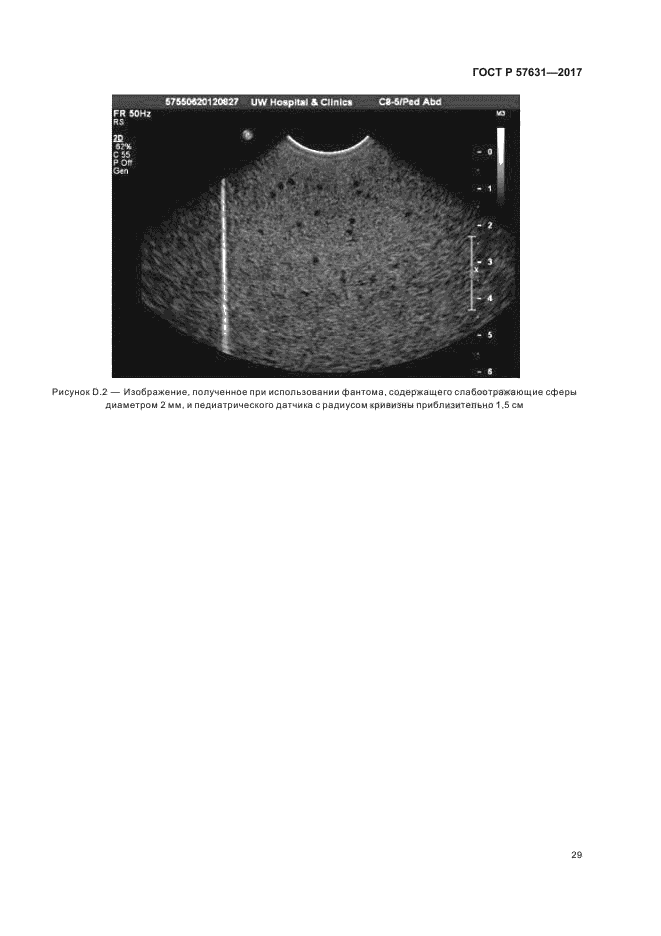

| Название рус.: | Техника ультразвуковая. Сканеры эхо-импульсные. Слабоотражающие сферические фантомы и методы испытаний для монохромных медицинских ультразвуковых аппаратов, применяемых с датчиками различных типов |

| Название англ.: | Ultrasonics. Pulse-echo scanners. Low-echo sphere phantoms and method for performance testing of gray-scale medical ultrasound scanners applicable to a broad range of transducer types |